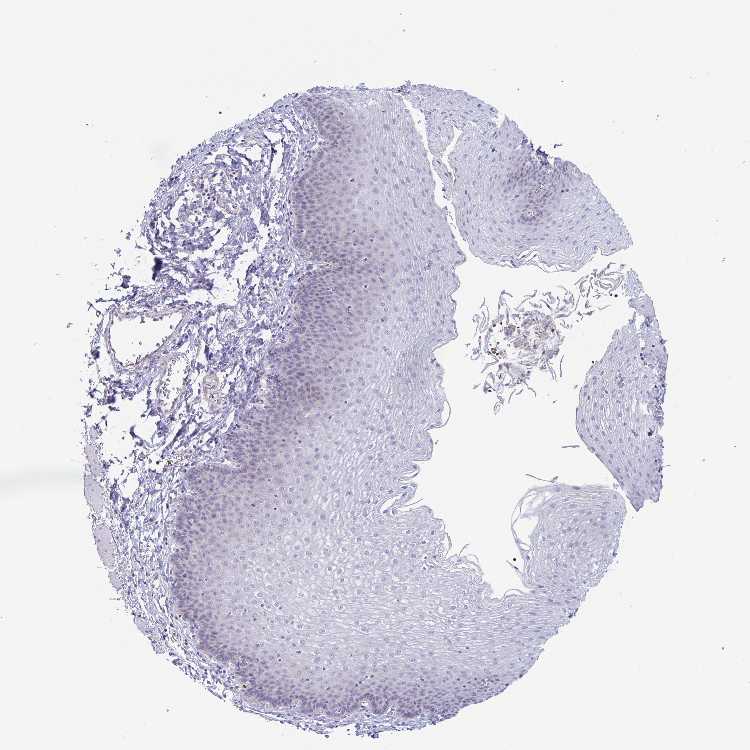

TISSUE PRIMARY DATA ESOPHAGUS Show tissue menu

Esophagus

ESOPHAGUS - Antibody stainingi

Antibody staining in the annotated cell types in the current human tissue is reported as not detected, low, medium, or high, based on conventional immunohistochemistry profiling in selected tissues. This score is based on the combination of the staining intensity and fraction of stained cells.

Each image is clickable and will lead to virtual microscopy that enables deeper exploration of all samples and also displays staining intensity scores, fraction scores and subcellular localization as well as patient and tissue information for each sample.

Antibody HPA051714Antibody HPA052100Antibody HPA052487

Squamous epithelial cells LowNot detectedNot detected